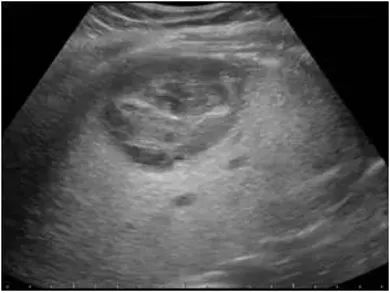

转移性肝癌

定义

● 是肝内最常见的继发性肝恶性肿瘤。

● 来源:转移性肝癌多来自于腹腔内肿瘤约占2/3,包括食管、胃肠道、胆囊、胰腺等消化系统恶性肿瘤居多。

● 不合并肝硬化。

病理特点:

瘤体快速增长,边缘瘤组织往往保持活跃的细胞生长结节内部,尤其瘤体中央区或中心发生不同程度缺血造成慢性组织变性、点片状坏死等不均质改变,伴随反复组织修复和结缔组织增生,有的发生液化坏死。

超声表现

● 圆形或椭圆形。

● 常多发,也可单发,在较大的转移性肝癌中可出现多结节相互融合,形似“葡萄串征。

● 内部回声多样,周边低回声的声晕(较宽)。

● 极少合并肝硬化。

● 少血供。